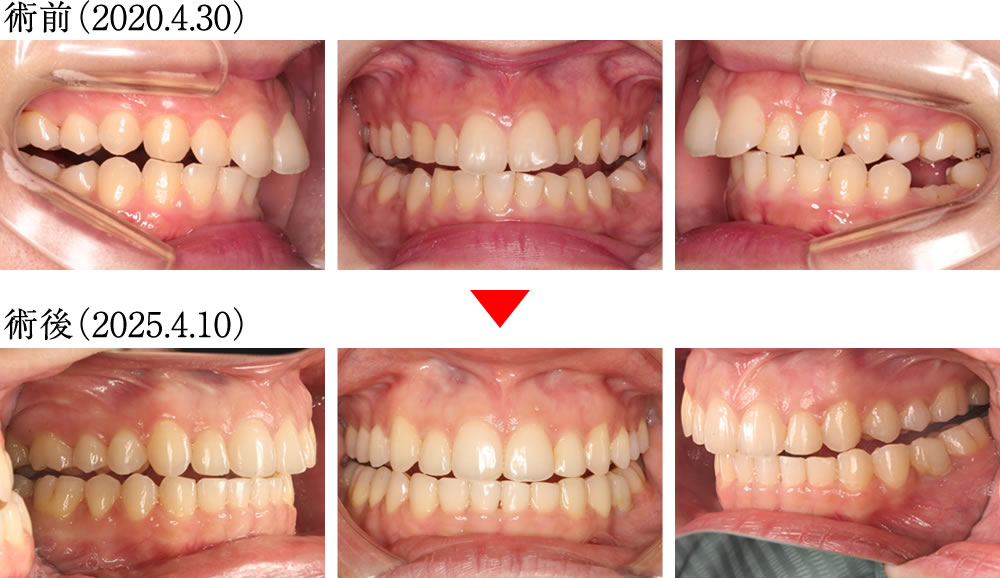

術前では、上顎の前歯が前方に傾斜しながら、深く噛みこんだ歯並びでしたが、術後は上下の歯が理想的な傾斜と被蓋関係で噛んだ歯並びになりました。

歯列が拡がったことにより、バッカルコリドー(笑った際に上の歯列と頬の内側との間にできる「黒い影」)が大きく改善されました。

術前では、歯列全体が狭く、不均衡に乱れたアーチの歯並びでしたが、術後は理想的に並んだキレイで大きなアーチになりました。